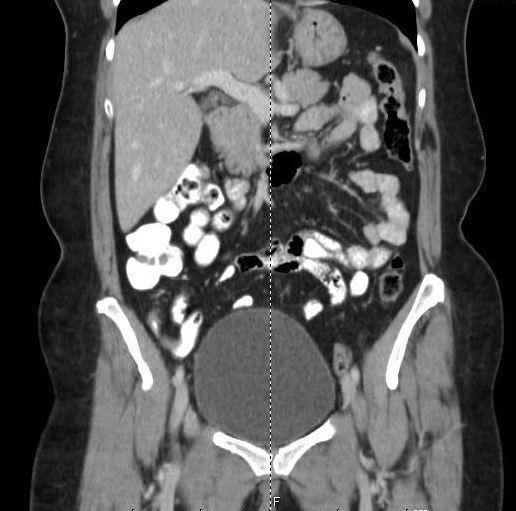

A computed tomography (CT) scan of the abdomen and pelvis with oral and intravenous contrast identified contrast in the base of the appendix but not the tip (Figures). The tip appeared mildly thickened, measuring approximately 6 to 9 mm, with hazy infiltrative change adjacent to it. Numerous clustered subcentimeter lymph nodes in the right lower quadrant also were identified, making the diagnosis consistent with acute appendicitis.